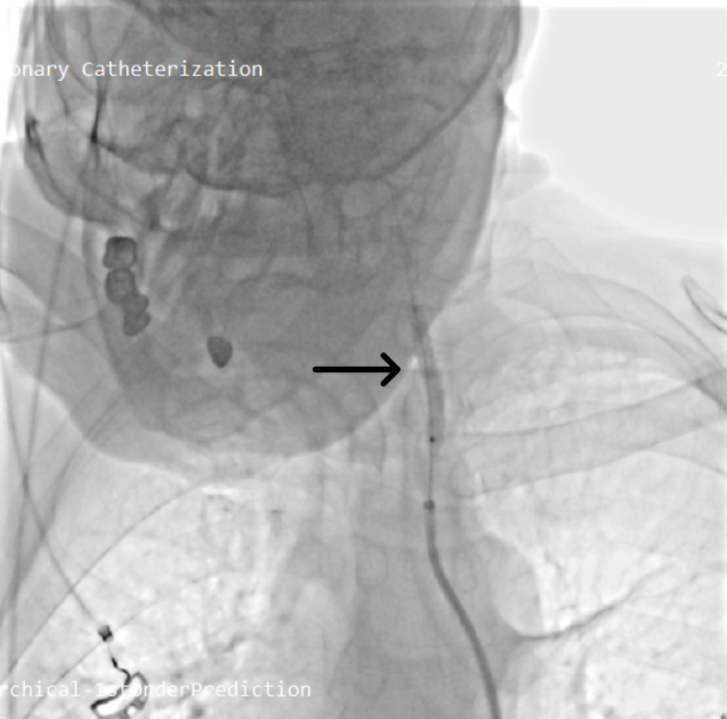

The bleeding segment was selectively wired. A 5 × 40-mm covered stent graft was deployed across the ruptured segment (Figure 2, Video 2); initial deployment was complicated by proximal slippage but hemostasis was ultimately achieved. The stent was then post-dilated with a 7 × 20-mm balloon to optimize apposition (Figure 3, Video 3). Final angiography confirmed complete sealing of the rupture and restoration of antegrade carotid flow (Figure 4, Videos 4 and 5).